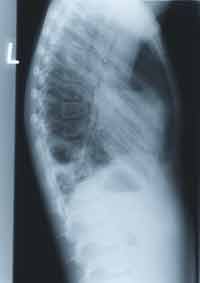

BELOW, CHEST X-RAY from October 1998.

Enlarge the CHEST X-RAY LEFT, enlarge the chest x-ray RIGHT.

WHAT ARE YOUR FINDINGS. WHAT WOULD YOU DO NEXT?